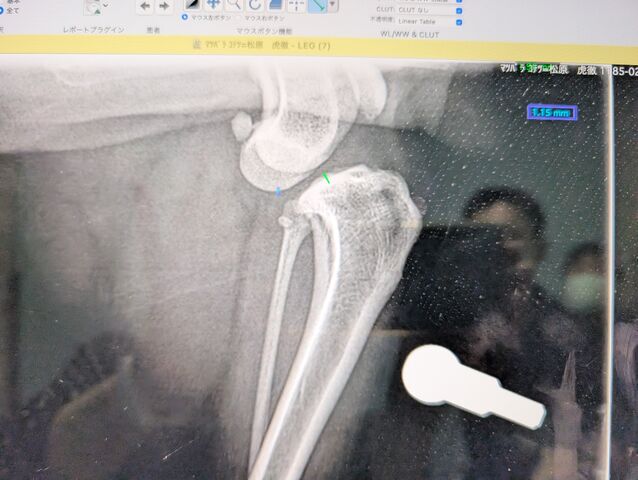

¸×Ű¤Îº¸É¨¤¬Á°½½»ú¿ÙÂÓÃÇÎö¤Ë¤Ê¤ê£±£°·î£¹Æü¤Ë¼ê½Ñ¤ò¤·¤Þ¤·¤¿¡£

¤³¤Ã¤Á¤¬ÃÇÎö¤·¤¿º¸É¨

´°Á´¤Ë¥º¥ì¤Æ¤Þ¤¹¡£